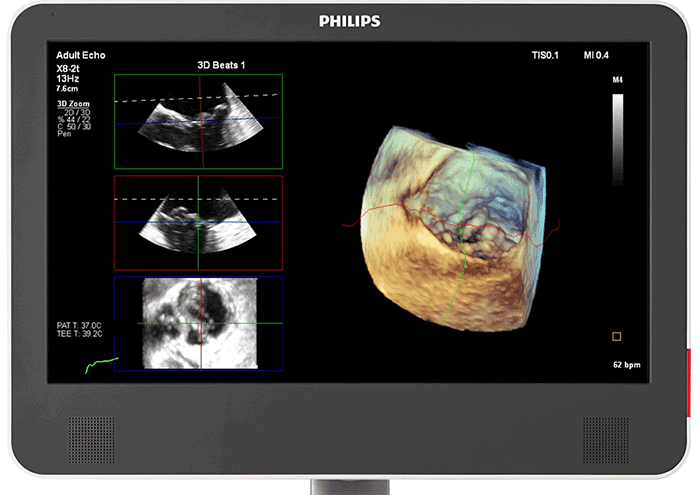

3D photorealistic rendering with virtual light source For improved visualisation of cardiac anatomy in the transthoracic and transesophageal echo, Philips cardiology TrueVue with its virtual light source makes it simpler to visualise the location of defects and comprehend depth within the structures. 90% of clinicians5 who saw the new Philips EPIQ CVx felt that the new TrueVue 3D photorealistic rendering provided improved viewing of anatomical structures, thus increasing clinical confidence.

Designed for next-generation Live 3D TEE The acoustic design of the Philips X8-2t Live 3D transesophageal transducer provides higher frequencies and bandwidth for increased resolution and tissue filling in 2D and Live 3D. It brings true one-beat acquisitions and our highest volume rates in Live 3D and Live 3D colour flow without compromise to image quality. Its handle is designed with a real-time configurable function button allowing for additional functionality while imaging.

Photorealistic rendering built for collaborative intervention suites For better visualisation of interventional devices, Philips cardiology TrueVue, with its virtual light source, is a proprietary and advanced 3D ultrasound display method. TrueVue makes it simpler to visualise the location of catheters and devices by providing images with tissue detail and depth perception. Since it offers a viewing context for the echo images, caregivers in the interventional suite can rely on support when communicating complicated echo images and enhance their procedural confidence. 90% of clinicians5 who saw the new Philips EPIQ CVx felt the new TrueVue 3D photorealistic rendering improved viewing of anatomical structures thus increasing clinical confidence2.